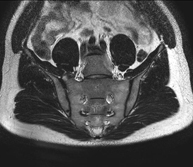

- RM de Sacroilíaques

Prova diagnòstica no invasiva que consisteix en l'obtenció d'imatges d'alta definició anatòmica de les articulacions sacroilíaques mitjançant l'ús d'un camp electromagnètic i ones de ràdio (amb un emissor i un receptor). No utilitza radiació ionitzant. Indicacions: dolor sacroilíac inflamatori. - RM ATM (Articulació temporo-mandibular)

- Sacroiliac MRI

Study specifically designed to assess these joints and their inflammation in patients suffering from ankylosing spondylitis. It is also useful in patients with trauma and possible fractures of the sacrum and coccyx. It lasts approximately 16 minutes. It is a radiation-free procedure.

- Sacrum-coccyx MRI

This non-invasive diagnostic procedure uses an electromagnetic field and radio waves (from a transmitter and receiver) to acquire high-definition anatomical images of the sacrum and coccyx. It is a radiation-free procedure. Indicated for: sacrococcygeal pain, trauma.